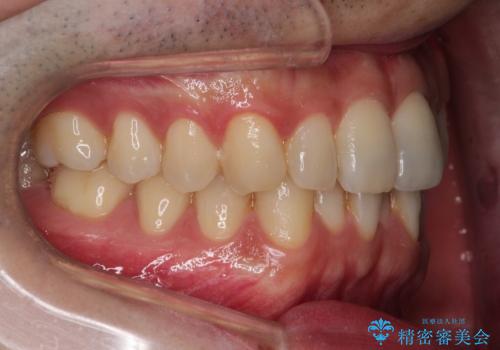

抜歯は行わず下顎の奥のスペースを利用して歯をスライドする方法の他に親知らずの抜歯そして上下ともに歯列弓の拡大やディスキング(歯と歯の間の隙間を作る処置)を行い叢生を改善しました。

矯正装置としてはマウスピースを使用しています。